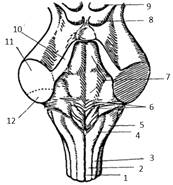

Строение сердца. Общие сведения

Сердце (cor) у человека четырехкамерное. В

сердце расположены продольные перегородки (межпредсердная -4 и межжелудочковая

– 14), которые делят орган на две изолированные половины – правое и левое

сердце, поперечная перегородка делит каждую из этих половин на верхнюю камеру –

предсердие и нижнюю – желудочек сердца.

Строение правого предсердия и желудочка

Правая половина сердца содержит венозную кровь и

состоит из правого предсердия (atrium dexstrum) и правого желудочка

(ventriculus dexter). Правое предсердие имеет форму куба, располагается в

основании сердца справа и позади аорты и легочного ствола. От левого предсердия

отделяется межпредсердной перегородкой (16), на которой находится овальная ямка

(15), которая является остатком овального отверстия через которое сообщаются

между собой предсердия во внутриутробном развитии. В правое предсердие впадает

верхняя полая вена (1), нижняя полая вена (14) и венечный синус (13). Верхняя

часть правого предсердия образована правым ушком сердца (5). Правое предсердие

сообщается с правым желудочком при помощи предсердно-желудочкового отверстия.

Правый желудочек имеет форму треугольной

пирамиды, с верхушкой обращенной вниз и располагается справа и спереди от

левого желудочка. От левого желудочка отделяется при помощи межжелудочковой

перегородки. Вверху в стенке желудочка есть два отверстия: сзади – правое

предсердно-желудочковое, а спереди – отверстие легочного ствола.

Предсердно-желудочковое отверстие закрывается при помощи трехстворчатого

клапана (8). Внутри правого желудочка находятся трабекулы и сосочковые мышцы,

от которых к створкам клапана идут сухожильные хорды. Из правого желудочка

начинается легочной ствол (6). Между правым желудочком и легочным стволом

находится полулунный клапан легочного ствола.

Строение левого предсердия и желудочка

Левая половина сердца содержит артериальную

кровь и состоит из левого предсердия (atrium sinistrum) и левого желудочка

(ventriculus sinister).

Левое предсердие имеет форму неправильного куба,

отграничено от правого межпредсердной перегородкой, имеет левое ушко (15). В

левое предсердие открываются 4 легочные вены, лишенные клапанов, они приносят

артериальную кровь от дёгких. С левым желудочком сообщается с помощью

предсердно-желудочкового отверстия, возле которого находятся гребенчатые мышцы.

Левый желудочек (16) конусовидный, его основание

обращено кверху. В переднем верхнем отделе желудочек сообщается с аортой. У

места выхода аорты из левого желудочка имеется клапан аорты, который состоит из

правой, левой и задней полулунных заслонок. В предсердно-желудочковом отверстии

располагается двухстворчатый клапан (митральный – 7).

На внутренней поверхности левого желудочка

находятся мясистые трабекулы (10) и две сосочковые мышцы (9), от которых идут

сухожильные хорды (8), прикрепляющиеся к свободным краям створок митрального

клапана.

Толщина стенок левого предсердия около 2 мм, а

желудочка – до 15 мм. Верхушку сердца полностью выполняет левый желудочек.

Строение перикарда, проводящая система сердца

Мускулатура предсердий и желудочков

функционально соединяется друг с другом при помощи проводящей системы сердца,

представляющей собой сложное нервно-мышечное образование. Проводящие волокна,

входящие в ее состав имеют особое строение: их клетки бедны миофибриллами, но

богаты саркоплазмой. В проводящей системе различают узлы и пучки: 1.

Синусно-предсердный узел (1) расположен в стенке правого предсердия. Он связан

с мускулатурой предсердий и обеспечивает их ритмическое сокращение. 2.

Предсердно-желудочковый узел расположен в стенке правого предсердия вблизи

трехстворчатого клапана (2). 3. Предсердно-желудочковый пучок (пучок Гисса – 3)

находится в перегородке между предсердиями и желудочками. 4. Ножки пучка Гисса

(4) находятся в мускулатуре желудочков. 5. Волокна Пуркинье (5) ветвятся под

эндокардом желудочков.